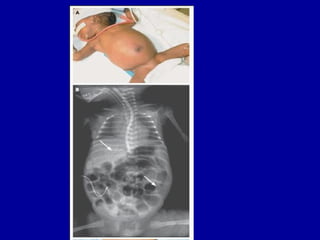

CLINICAL PRESENTATION

ABDOMINAL DISTENSION

SEVERE ABDOMINAL DISTENSION